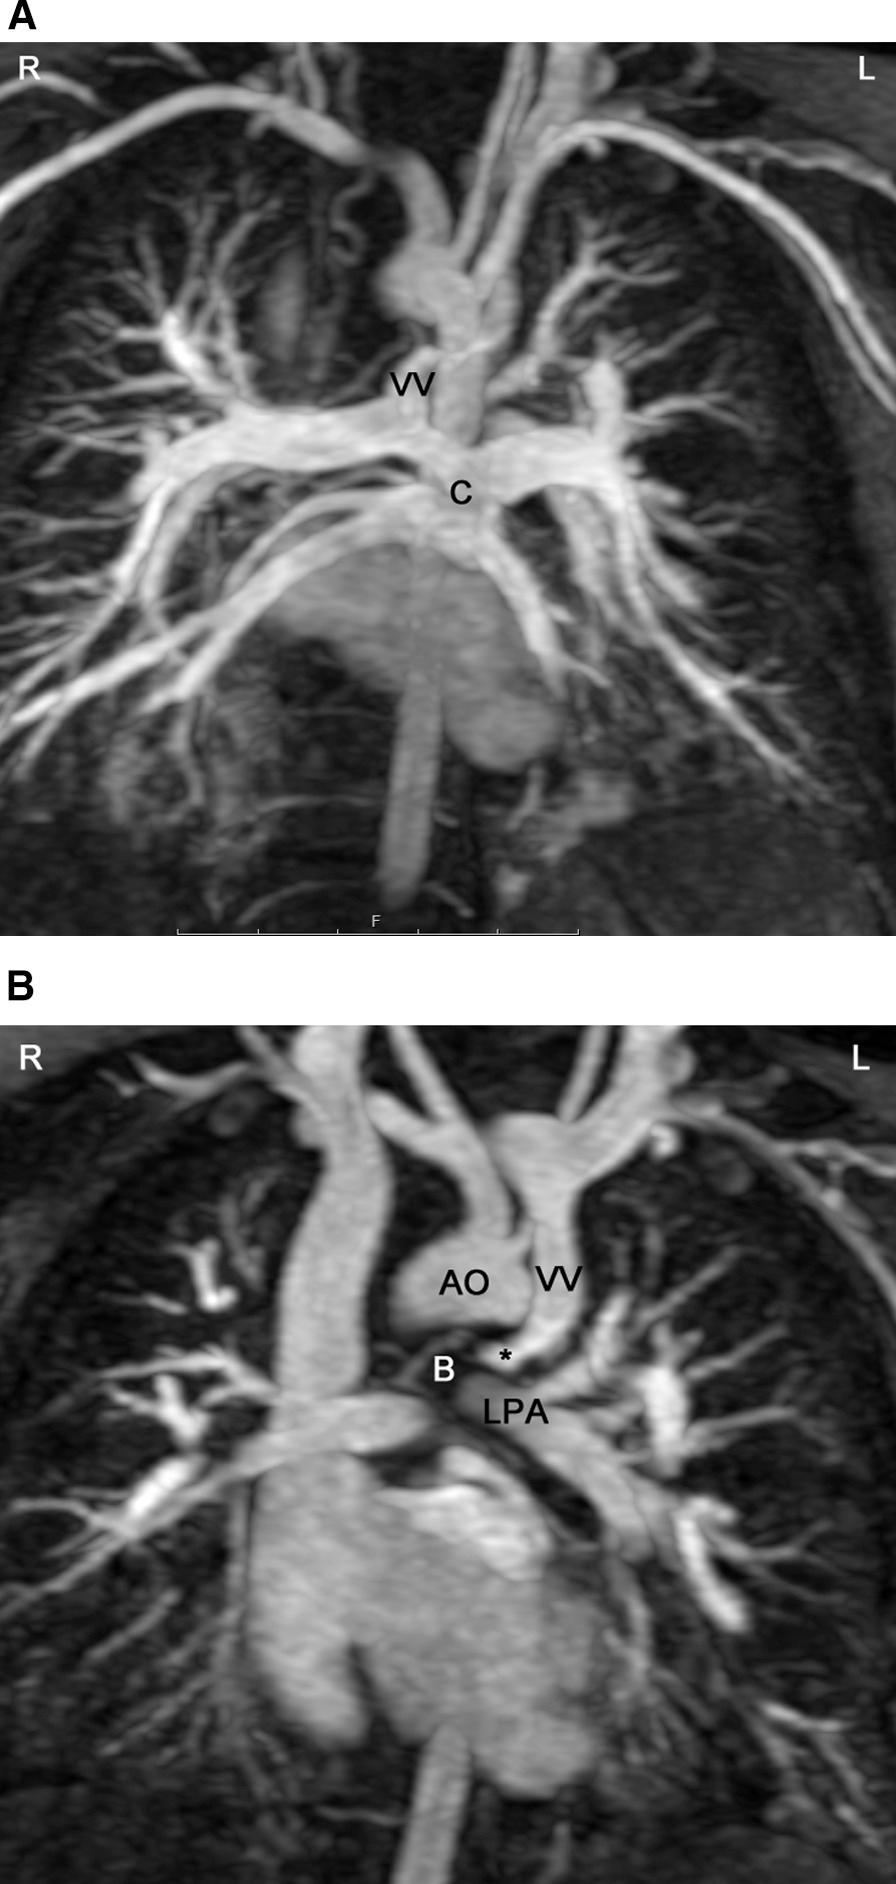

Cardiovascular magnetic resonance (CMR) has been utilized in the management and care of pediatric patients for nearly 40 years. It has evolved to become an invaluable tool in the assessment of the littlest of hearts for diagnosis, pre-interventional management and follow-up care. Although mentioned in a number of consensus and guidelines documents, an up-to-date, large, stand-alone guidance work for the use of CMR in pediatric congenital 36 and acquired 35 heart disease endorsed by numerous Societies involved in the care of these children is lacking. This guidelines document outlines the use of CMR in this patient population for a significant number of heart lesions in this age group and although admittedly, is not an exhaustive treatment, it does deal with an expansive list of many common clinical issues encountered in daily practice.

心血管磁共振(CMR)在儿科患者的管理和护理中已经应用了近 40 年。它已经发展成为评估最小的心脏的宝贵工具,用于诊断、介入前管理和随访。尽管在许多共识和指南文件中提到,但在儿科先天性心脏病和后天性心脏病领域,目前还缺乏一份由众多参与儿童护理的学会共同认可的、最新的、独立的、针对 CMR 使用的大型指南。本指南文件概述了 CMR 在该年龄段的许多心脏病变中的应用,尽管不能说是详尽的治疗方法,但它确实涉及了在日常实践中经常遇到的许多常见临床问题的广泛列表。